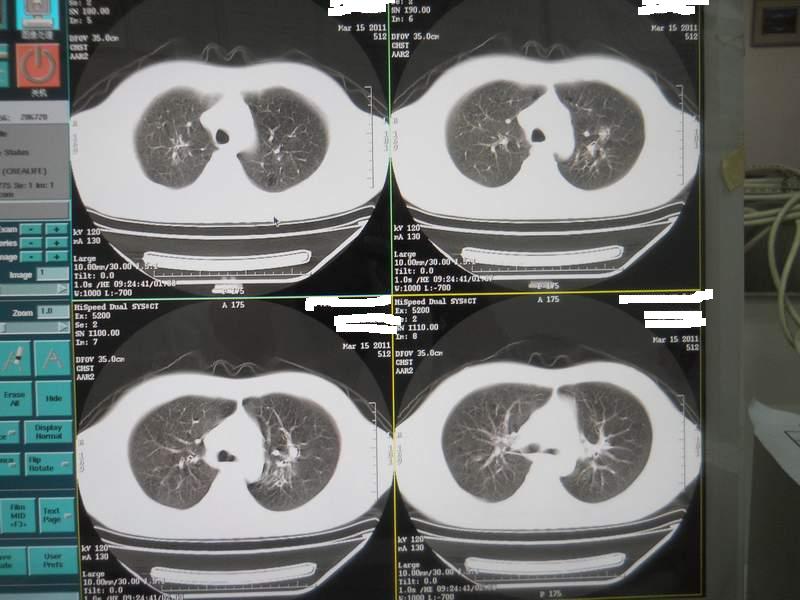

肺霉菌感染

男,22岁,一年前诊断马尔菲尼青霉菌感染,多次复查CT。多次HIV阴性。最近两次CT图片。有实验室结果。

最近实验室检查结果:霉菌感染。